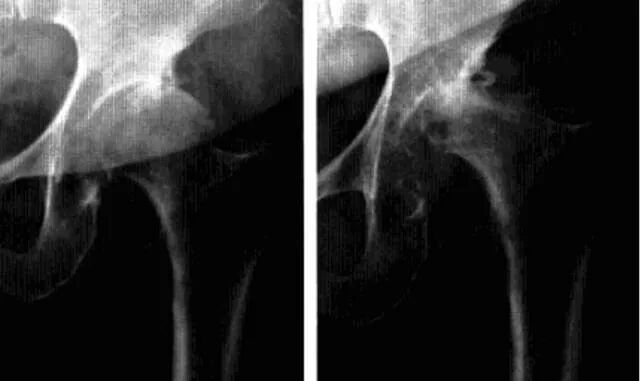

快速破坏性髋关节病

是一种不知确切病因而侵犯股骨头及髋臼导致髋关节在短时间内快速破坏的髋关节疾病。

影像诊断:首选X线平片,髋关节正位及蛙式位。

1、平片:髋关节间隙进行性消失是本病特征;早期股骨头无明显变化,数月间股骨头上方进展性破坏吸收,股骨头变扁,无囊变,骨赘增生不显著,周围软组织无明显异常。

2、CT:股骨头负重区骨质溶骨样改变,骨质碎裂的,关节面软骨大片状剥脱皲裂,头*骨质呈小圆形颗粒状改变,软骨下骨的连续性破坏,头外形不规则缺损,碎骨片线状分离。

3、MRI:股骨头及髋臼骨质吸收伴软骨丢失,股骨头向上外方移位,关节内积液,骨髓未见明显异常。